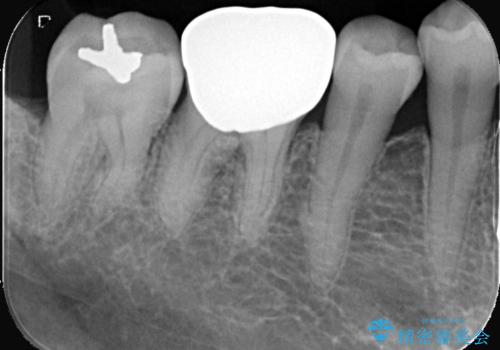

- 「銀歯を白くしたい」を主訴に来院された患者様です。銀歯を外し虫歯を除去後、オールセラミッククラウンで治療を行いました。

銀歯を外して内部の虫歯を丁寧に除去した後、オールセラミッククラウンにて修復を行いました。審美性と機能性の両面で改善が得られ、患者様にもご満足いただきました。